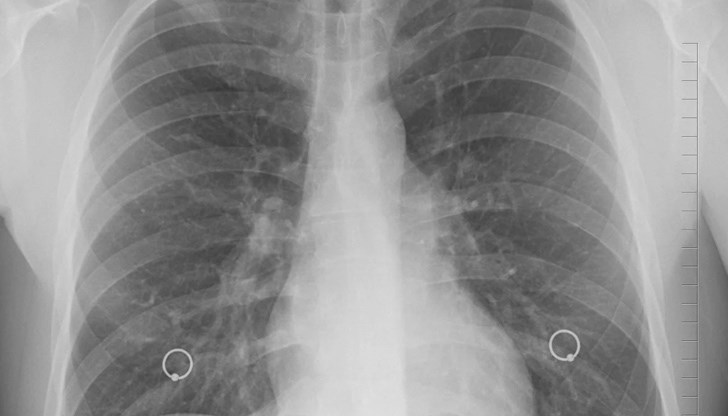

Основен фокус на епидемията от коронавирус, в която се намираме всички ние, е белият дроб. В тази връзка предлагам няколко начина как да подкрепите белия си дроб. Това е особено важно за хората с хронични белодробни проблеми, за тези, прекарали наскоро заболяване, за пушачите и пр.